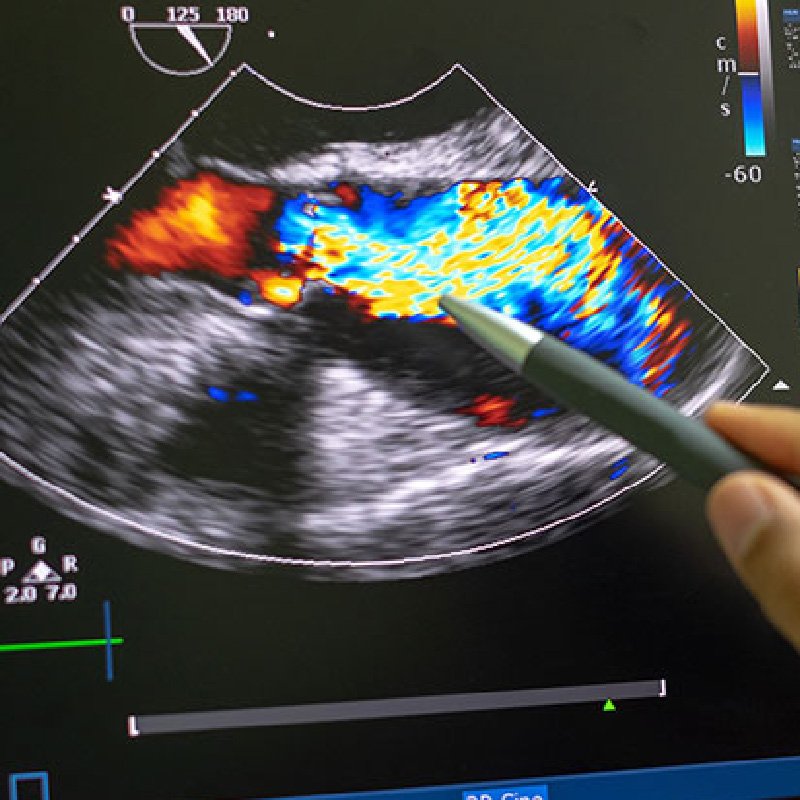

Ultrasonido Doppler

Visualización de vasos sanguíneos con mayor precisión para el diagnóstico